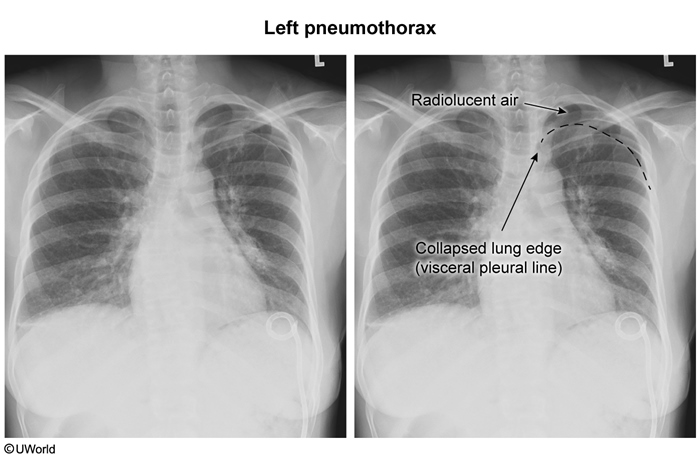

Pneumothorax

visceral pleural lines: